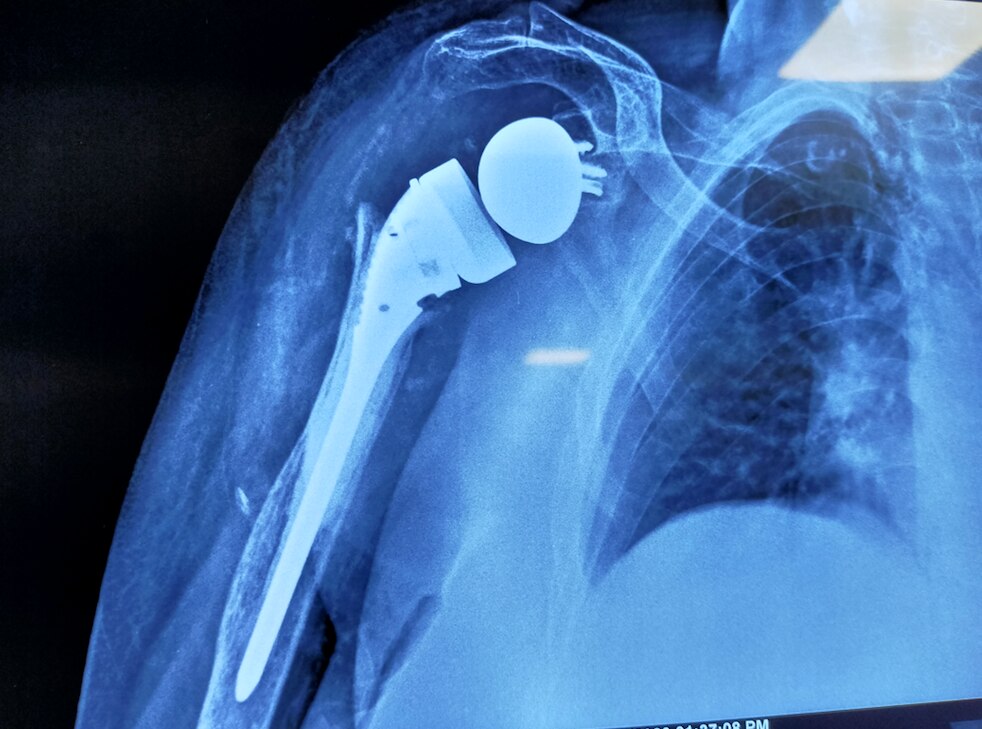

Dr Rahul Rane is an Orthopaedic Surgeon with 16 years of experience in the field of Orthopaedics. He has taken his Master's Degree in Orthopaedic from Mumbai's reputed Lokmanya Tilak Medical College. He has vast experience in treating all kinds of Orthopaedic and Spine problems He is a master in Spine surgery with cutting-edge Endoscopic spine Surgery techniques with no complications. Patients can walk on the same day after endoscopic spine-surgery. He had done Advance Spine Surgery fellowship Training in Korea. He performs all kinds of joint replacement surgeries with excellent results. His operated knee and Hip replacement patients walk full weight bearing after 1 day. His patient's post Surgery walking freely and performing all kinds of work. He is a fitness freak, an avid Marathon runner. He is passionate about making his patients recover faster. “My patient should resume to routine earliest” is his motto.